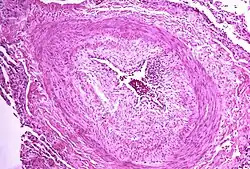

The pathogenesis of pulmonary arterial hypertension (WHO Group I) involves the narrowing of blood vessels connected to and within the lungs. This makes it harder for the heart to pump blood through the lungs, as it is much harder to make water flow through a narrow pipe as opposed to a wide one. Over time, the affected blood vessels become stiffer and thicker, in a process known as fibrosis. The mechanisms involved in this narrowing process include vasoconstriction, thrombosis, and vascular remodeling (excessive cellular proliferation, fibrosis, and reduced apoptosis/programmed cell death in the vessel walls, caused by inflammation, disordered metabolism and dysregulation of certain growth factors).[27][28] This further increases the blood pressure within the lungs and impairs their blood flow. In common with other types of pulmonary hypertension, these changes result in an increased workload for the right side of the heart.[16][29] The right ventricle is normally part of a low pressure system, with systolic ventricular pressures that are lower than those that the left ventricle normally encounters. As such, the right ventricle cannot cope as well with higher pressures, and although right ventricular adaptations (hypertrophy and increased contractility of the heart muscle) initially help to preserve stroke volume, ultimately these compensatory mechanisms are insufficient; the right ventricular muscle cannot get enough oxygen to meet its needs and right heart failure follows.[16][28][29] As the blood flowing through the lungs decreases, the left side of the heart receives less blood. This blood may also carry less oxygen than normal. Therefore, it becomes harder and harder for the left side of the heart to supply sufficient oxygen to the rest of the body, especially during physical activity.[30][31][11] During the end-systolic volume phase of the cardiac cycle, the Gaussian curvature and the mean curvature of the right ventricular endocardial wall of PH patients were found to be significantly different as compared to controls.[32]